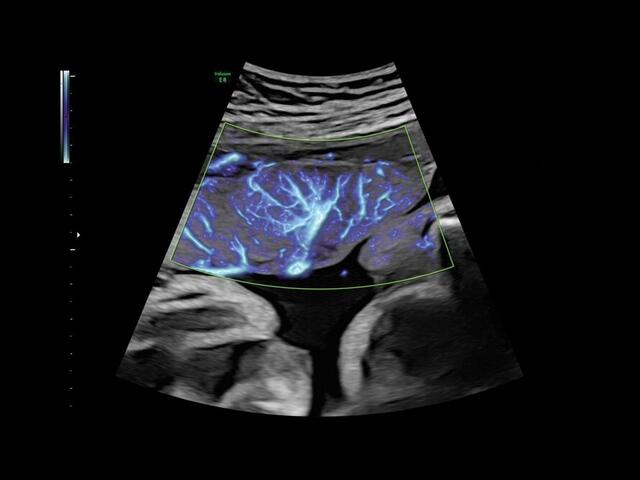

• HD-FlowTM для точного изучения кровотока и прорисовки сосудов.